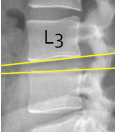

Q what is the name of this measurement? and what is the average + range?

A: Lumbar Gravity Line

assesses the alignment of the L3 vertebral body with the sacrum. The line should intercept the sacral base